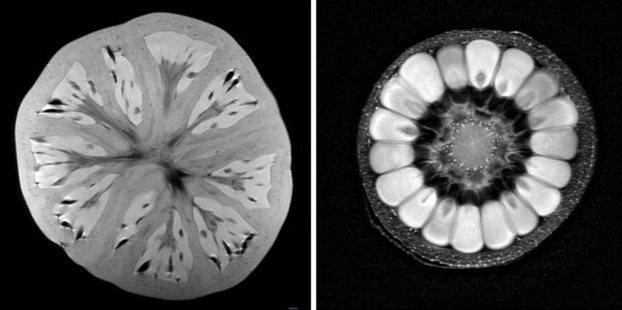

Κινέζοι ερευνητές ανακοίνωσαν ότι χάρη σε μια ειδικά σχεδιασμένη τεχνική μαγνητικής απεικόνισης μπορούν να εντοπίσουν μη φυσιολογικές συνδέσεις στους εγκεφάλους των παιδιών προσχολικής ηλικίας με αυτισμό, σύμφωνα με άρθρο που δημοσίευσαν στο επιστημονικό έντυπο Radiology.